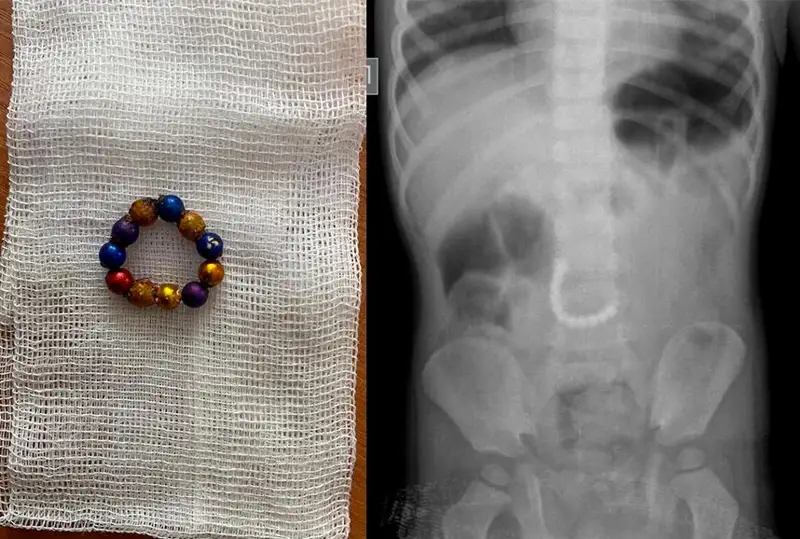

Врачи спасли проглотившего 11 магнитов мальчика в Караганде